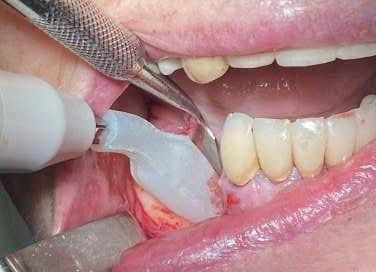

Le innovazioni tecnologiche per l’efficace mantenimento delle riabilitazioni implantari

La prevenzione terziaria è una vera sfida per l’igienista dentale, che per competenza del suo profilo professionale ha la gestione del mantenimento delle riabilitazioni odontoiatriche.

Le terapie riabilitative implantari per pazienti con edentulia parziale o totale, permettono di riportare sia la funzionalità che l’estetica, con una prevedibilità di successo che dipende, oltre che dall’efficace piano terapeutico chirurgico implantare del professionista chirurgo, anche dalla responsabilità attiva del paziente a seguire corretti stili di vita di igiene orale domiciliare e follow-up. Questi devono prevedere la visita diagnostica di controllo dell’implantologo e la visita di controllo dell’igienista dentale. Per sollecitare l’aderence ai follow-up, usare l'automazione workflow e moduli di anamnesi personalizzati (gestionale Alfa Docs) permette una migliore gestione e un monitoraggio efficace delle cure e dei richiami personalizzati in base ai bisogni extra clinici dei pazienti. La vera sfida è il management di igiene orale in pazienti presi in carico che sono stati sottoposti a terapie implantari in altri studi, e che mostrano clinicamente mucosite, con interessamento della mucosa perimplantare o con perimplantite che coinvolge l’osso di sostegno.

Spesso si evidenzia il collare implantare degli abutment, e prima che l’implantologo preveda intervento mucogengivale è fondamentale condividere con il paziente la necessità di eliminare l’infiammazione eseguendo un'igiene orale domiciliare attenta ed efficace. L'igiene orale domiciliare deve essere considerata terapia.

biofilm batterico domiciliare. Per il controllo meccanico del biofilm batterico, se viene lamentata dolorabilità, si deve concordare l'uso di uno spazzolino con setole che siano efficaci ma che non creino dolorabilità durante l’utilizzo (GUM Sonic Sensitive).

(olio extravergine di oliva ozonizzato, acido ialuronico, aloe vera, cetilpiridinio cloruro, ratania) accelera il processo di guarigione, riduce la risposta infiammatoria e l'edema (sciacquo è di 1 minuto ripetuta fino a due volte al giorno). La terapia parodontale non chirurgica è fondamentale per i follow-up a medio e lungo termine per il paziente con riabilitazione implantare.

Bisogna accertarsi che non sia presente pus, sintomo predittivo di perimplantite e probabile perdita ossea, che va valutata dall’implantologo radiograficamente, con particolare attenzione alla perdita ossea interprossimale. Se presente, è importante l’approccio motivazionale di concordance con la persona assistita per responsabilizzarlo al controllo del biofilm batterico degli spazi interprossimali

Successivamente alla diagnosi ricevuta dall’implantologo e le indicazioni sul piano terapeutico scelto, capita spesso di intervenire con una terapia di supporto palliativa, che ha l’obbiettivo di mantenere le condizioni della riabilitazione in buon stato clinico. L’ascolto del paziente è fondamentale per accogliere i disturbi percepiti dal paziente quali disestesia, sensazione di corpo estraneo o dolore.

L’utilizzo degli scovolini in gomma, (GUM Soft Picks Confort Flex), risultano essere delicati sui tessuti perimplantari, ed efficaci, grazie alle differenti misure possibili, per la personalizzazione della scelta dell’interprossimale a seconda dello spazio sovracrestale.

L’evoluzione di tecnologie così sofisticate ha permesso di poter offrire l’opportunità di fare “la giusta scelta” personalizzata per ogni caratteristica anatomica, di maualità e predisposizione di fragilità, o soltanto seguire l’approccio caratteriale del paziente.

(TBM) Nardi G.M. et al. Tailored Brushing Method (TBM): an innovative simple protocol to improve the oral care. J Biomed 2016; 1:26-31. Il protocollo di igiene orale deve essere personalizzato in base alla tipologia del manufatto protesico implantare, poiché spesso la persona assistita ha difficoltà di efficacia nel controllo del

Per il controllo chimico del biofilm batterico domiciliare, l’olio di oliva ozonizzato è molto apprezzato dalla persona assistita poiché ha un gusto gradevole, non crea discromie sulle superfici dentali e implantari e può essere usato quotidianamente, aspetti che non vanno trascurati poiché permettono compliance e maggiore aderence alle terapie di igiene orale domiciliare.

L’uso del colluttorio all’olio di oliva ozonizzato Ialozon Blu (GEMAVIP),

L’ aMMP-8 (metalloproteinasi di matrice attiva) è un biomarker per la diagnosi precoce di malattie gengivali, processi degenerativi dei tessuti molli e duri a livello parodontale e perimplantare. La presenza di aMMP-8 si riscontra prima di qualsiasi segnale di infiammazione o perdita di tessuto. Dalla valutazione di efficacia della terapia parodontale non chirurgica coadiuvata dall’utilizzo di collutorio a base di olio ozonizzato, sui valori oggettivi di Metalloproteasi salivare (MMP-8) nel paziente affetto da parodontite, è stato evidenziato che lo SRP coadiuvato dall'utilizzo domiciliare di collutorio a base di olio ozonizzato contribuisce ad un più accentuato miglioramento dei parametri clinici parodontali Nardi GM, Cesarano F, Papa G, Chiavistelli L, Ardan R, Jedlinski M, Mazur M, Grassi R, Grassi FR. Evaluation of Salivary Matrix Metalloproteinase (MMP-8) in Periodontal Patients Undergoing Non-Surgical Periodontal Therapy and Mouthwash

Based on Ozonated Olive Oil: A Randomized Clinical Trial. Int J Environ Res Public Health. 2020 Sep 11;17(18):6619. doi: 10.3390/ijerph17186619. PMID:32932898; PMCID: PMC7558934. IF:3,390, Evidenze scientifiche hanno dimostrato che gli ozonidi selezionano la crescita di un microbiota più favorevole all’eubiosi del cavo orale limitando la proliferazione di microrganismi opportunistici.

L’uso di ablatori che permettano in maniera ergonomica di erogare deplaquing e debridment con la possibilità di scelta di differenti punte per un migliore adattamento alla superficie sono ideali per una terapia parodontale non chirurgica efficiente, ed un timing operativo agevole per l’ope-

ratore e per il paziente (Combi Touch Mectron). Il sondaggio parodontale permette la diagnosi della malattia perimplantare e va eseguito con una sonda in materiale plastico con delicatezza ed una forza controllata di 0.25 N, per evitare danni alla mucosa perimplantare. In caso la sonda evidenzi una tasca perimplantare, può essere usato il gel Perioral 3 (GEMAVIP) all’olio di oliva ozonizzato.